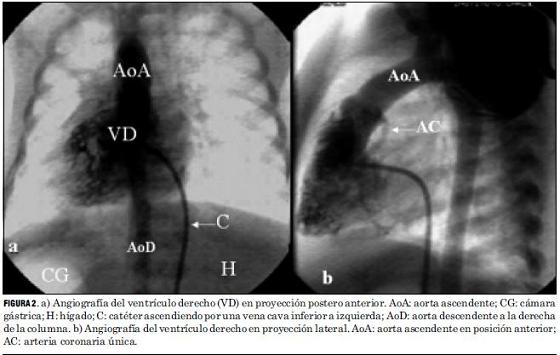

El análisis anatómico destaca que 40 pacientes presentaron D-TGA con séptum interventricular intacto y 20 con comunicación interventricular. Uno de estos pacientes asoció una coartación de aorta con severa hipoplasia del arco aórtico, otro era portador de un situs inversus (figuras 2 y 3), y otro presentaba una estenosis subpulmonar leve (tabla 4, figura 4).